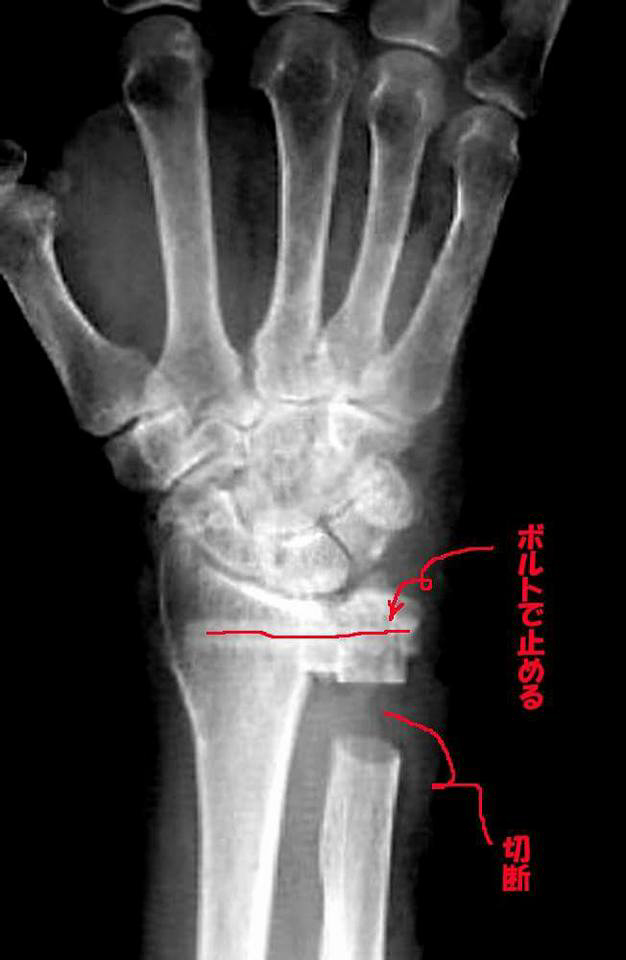

2017年1月5日、ハーレーのシート下にあるバッテリーを両手で掴んで取り出そうとした時、右手小指と薬指から鈍い「ブチッ」と音がした。その時は痛くなかったが数日すると、小指、薬指が「くの字」のままで真っすぐにしようとすると痛みが走り、その後、その痛みは激しさを増し、「手外科」のお世話になる事になった。精密検査結果、小指と薬指の「腱が切断」そして右手くるぶしの軟骨消耗!

手術しないと悪化する一方で「放って置くと右手が使えなくなる!そして4時間かけて写真の手術であった。

ボルトやナットで固定し、右手の骨の一部切断で空間を作り、この部分が摺動してくるぶしの役割を果たす、その手術であった。

当初は「小指の腱は切断されている」と言う症状であったが、検査していくうちに「くるぶしの不都合」も露見で、腱切断修正は腱移植手術と一緒行い、再度手術をしないで済むよう主治医が取り図ってくれた。